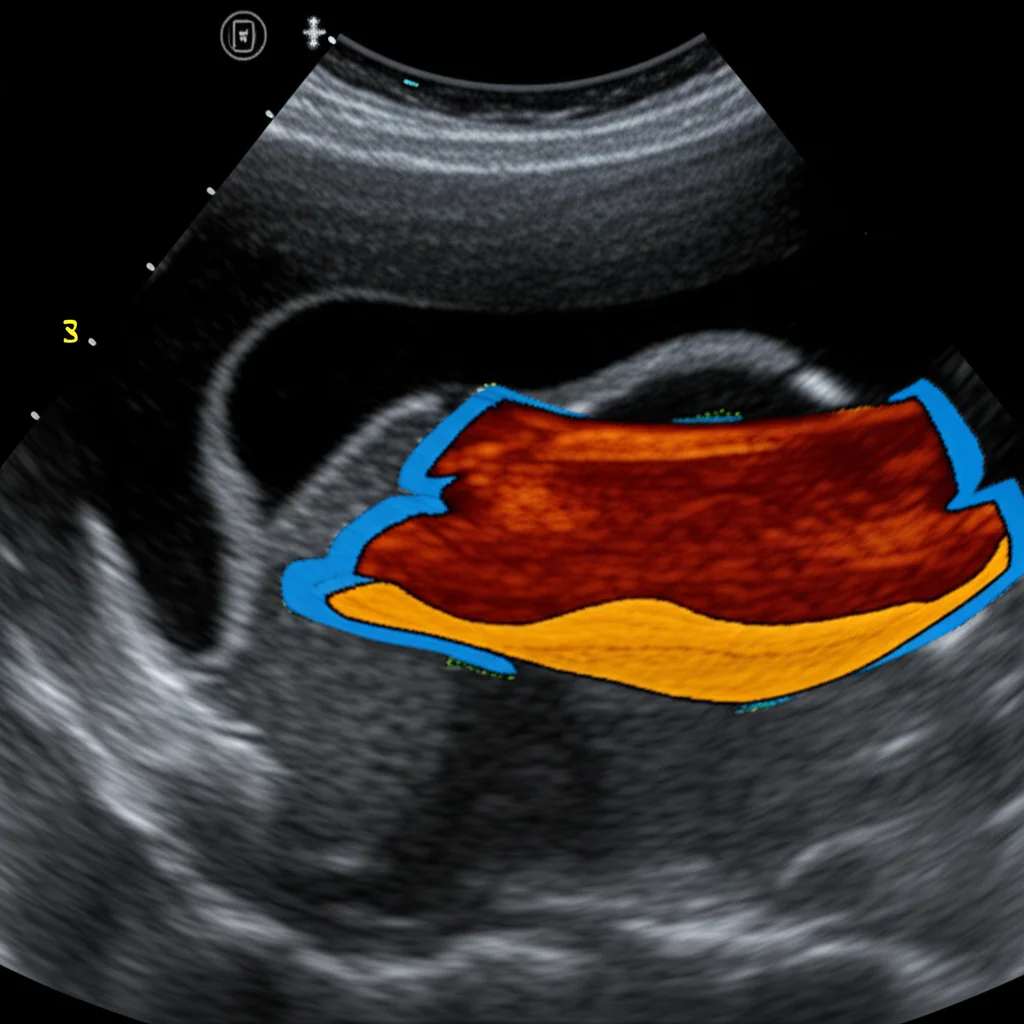

Before feeding the images into the network, we did some standard cleanup: cropping the interesting part, resizing everything to a consistent size (256×256 pixels), and normalizing the image data. We also had to meticulously label the images, outlining the TLF itself, the tissue above it, and the tissue below it (including the epimysial fascia covering the muscles).

So, how did our digital assistant perform? The U-Net model learned remarkably well, achieving a final training accuracy of 0.99 and a validation accuracy of 0.91. When we tested it on the unseen images from Test set 1, the prediction accuracy was 0.94. We also looked at other standard metrics like the mean Intersection over Union (IoU) index (0.82) and the Dice-score (0.76), which measure how well the predicted outline matches the actual outline.

Here’s where it gets really interesting: on Test set 2, the one collected from a totally different setup, the results were even *better*! We saw a mean IoU of 0.85 and a Dice-score of 0.91. This was fantastic news because it strongly suggests the method isn’t just specific to one lab or one machine.

And because numbers only tell part of the story, we had two expert clinicians visually inspect the segmentations produced by our model. They confirmed that the predictions were valid and accurate.